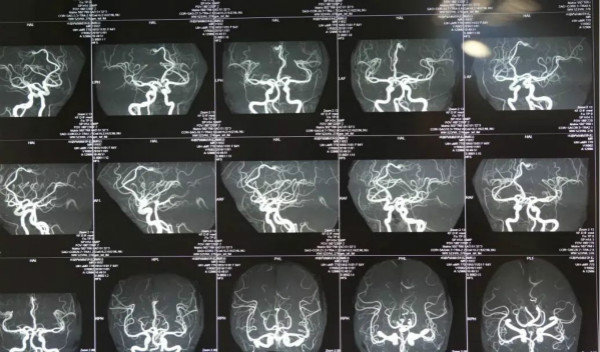

腦動(dòng)脈瘤多為發(fā)生在顱內(nèi)動(dòng)脈管壁上的異常膨出,是造成蛛網(wǎng)膜下腔出血的主要病因,在腦血管意外中,僅次于腦血栓和高血壓腦出血,那么腦動(dòng)脈瘤對(duì)患者的生存時(shí)間有影響嗎?